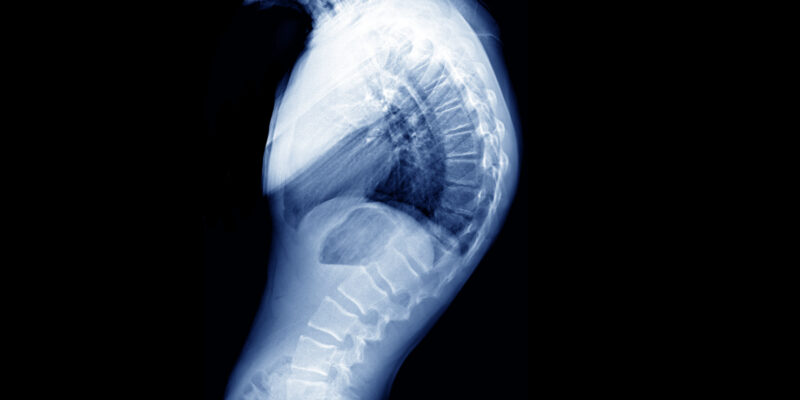

Kyphosis is when the upper spine curves outward more than is normal, making the back appear more rounded. It is normal to have up to a 45° curve.

The surgeon in clinic will perform a physical examination to determine the flexibility of the curve. X-rays will be taken and questions asked about the problems and concerns you have, together with a brief medical history. You may also be referred for a MRI scan.

Sometimes kyphosis can be caused by a problem with the way the spine grows and develops. The back of the vertebrae in the upper part of the spine can grow more quickly than the front, causing the vertebrae to grow into a wedge shape. If this happens to several vertebrae, it causes the spine to curve.

This is known as Scheuermann’s kyphosis and often occurs in adolescents. If the rounded back cannot be straightened, the cause of the curve is more likely to be a problem with the spine like Scheuermann’s. This is the most common cause of structural kyphosis in adolescents.